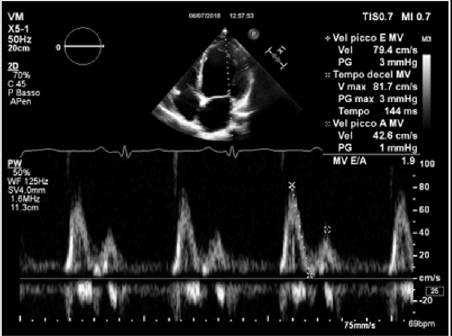

Physical examination showed a muscular man, the apex beat was not evident, the jugular at baseline showed an absent X’ descent with a positive hepato-jugular reflux and heart sounds were regular at the auscultation ; there was also minimal ankle swelling and , bilateral basal crackling rattles were audible at lung auscultation. The ECG showed a sinus rhythm with a frequency of 88 bpm, signs of left atrial enlargement, a left axial deviation and negative T-waves on D1 and aVL and from V4 to V6; no previous recent ECG was available for comparison. Chest X-ray showed pulmonary edema and an acute bronchopneumonia focus. Transthoracic echocardiography (TTE) revealed a dilated cardiomyopathy with severe left ventricular systolic dysfunction (LVEF 23% calculated with the Simpson biplane method) and dilatation (telediastolic diameter 79 mm) with moderate uniform hypertrophy (Figure 1a & 1b). There was grade II diastolic dysfunction (E/A waves ratio 1,9; E wave deceleration time 144 msec), “B-bump” on M-mode examination at the mitral valve level and an average E/e’ at tissue doppler analysis at the upper limit of the “grey zone”: 14 (Figure 2a-2d); global longitudinal peak systolic strain (GLPSS) was -7,4%; the left atrium was dilated; the right ventricle was dilated, slightly hypocontractile (tricuspidal annular plane systolic excursion, TAPSE, 16 mm) with a dilated right atrium; the inferior cava vein showed a normal dimension and collapsibility.

Figure 2c: An average E/e’ ratio at TDI analysis at basal septal and lateral level of 14 (grey zone).